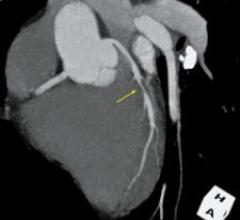

CT technology is moving into new imaging arenas such as cardiology, neurology and trauma, giving clinicians the ability…